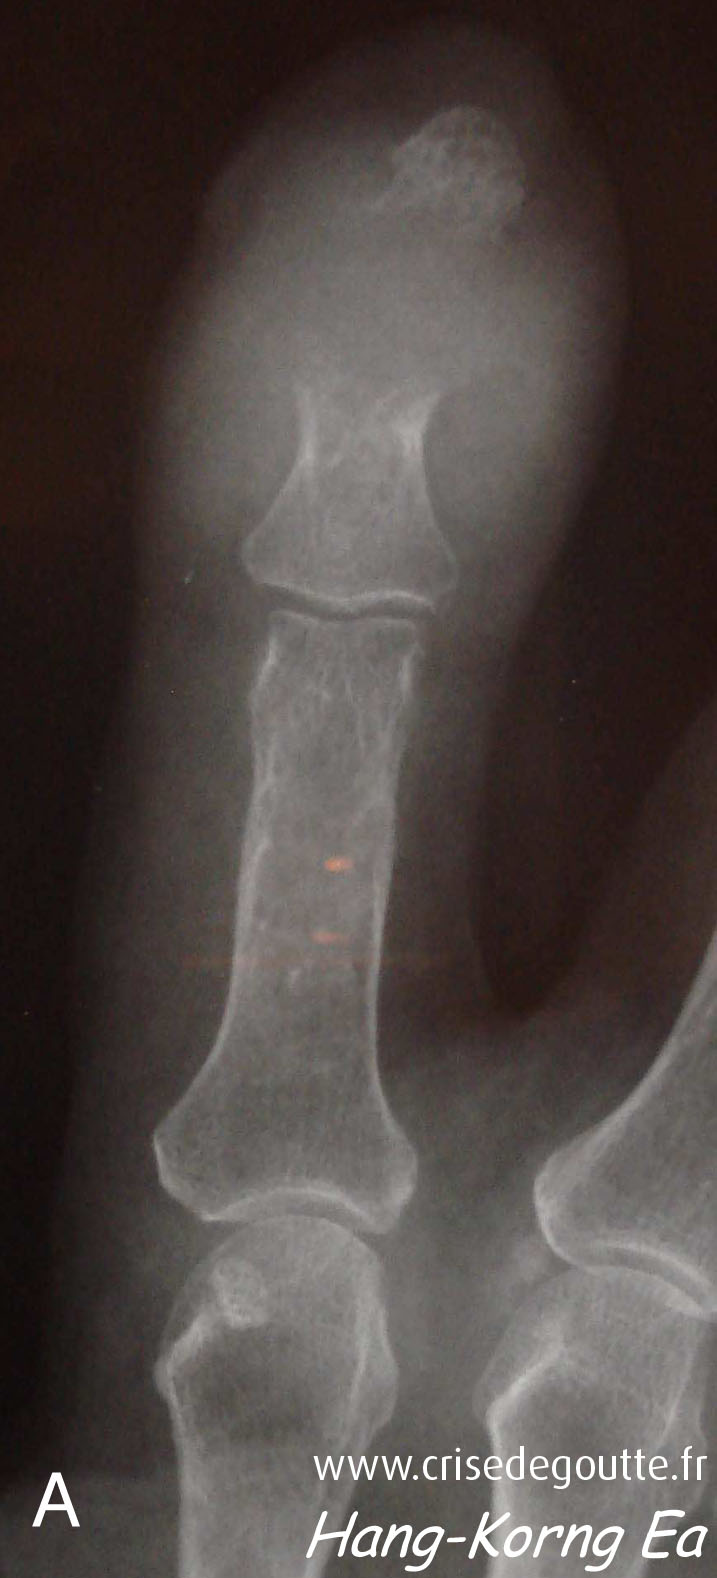

Imagerie

Tophus